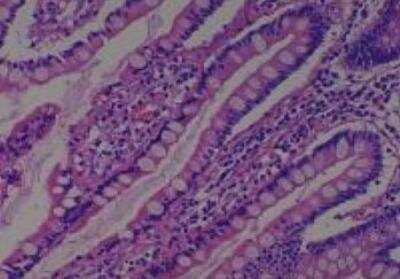

Hematoxylin & Eosin Stain: Human Common Tissue MicroArray (Normal Adjacent) [NBP2-30215] - 01. Stomach

Hematoxylin & Eosin Stain: Human Common Tissue MicroArray (Normal Adjacent) [NBP2-30215] - 102. Stomach

Hematoxylin & Eosin Stain: Human Common Tissue MicroArray (Normal Adjacent) [NBP2-30215] - 103. Stomach